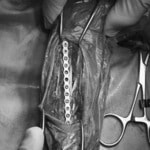

トイプードル 右遠位橈尺骨短斜骨折のALPSによる内固定

当院ではAdvanced Locking plate system(ALPS)と、Locking compression plate system(LCPS)という骨接合法で骨折症例の治療を行っています。

従来型のプレートのように広い面積で骨と接するプレートを用いて固定を行った場合、プレート下の骨はプレートとの接触面において血行が絶たれ壊死し、それがリモデリングされると骨密度が低下する。この骨密度の低下防ぐために、骨折部局所への血行を温存することの重要性が近年改めて認識されるようになってきている。Advaed Locking Plate System (ALPS)は従来型のプレートシステムの欠点を改良し、より使いやすく、より骨への血行を阻害しないようにというコンセプトで作られた。